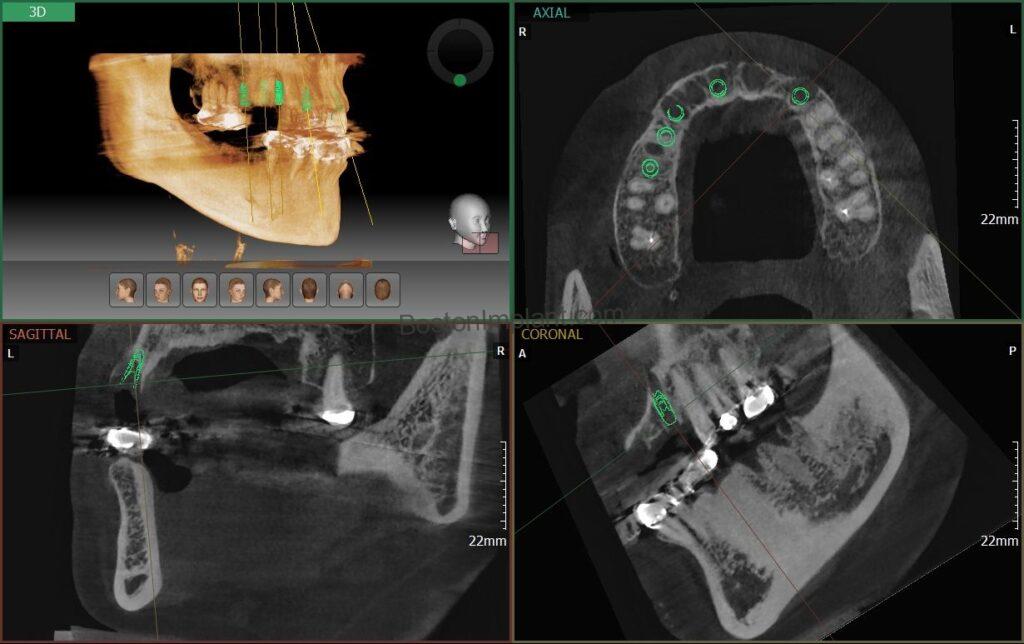

To thoroughly understand her bone structure, we began with a CBCT (Cone Beam Computed Tomography) scan, a sophisticated 3D X-ray providing a detailed blueprint of her jaw. Following a comprehensive consultation and the development of a tailored treatment plan, we decided on the placement of 12 dental implants. For optimal aesthetics in the upper front, we planned for tooth-colored abutments, while utilizing titanium abutments on the molars for enhanced durability. (You can learn more about these components in our blog post, ‘Custom Abutments of Dental Implants‘.) While our initial aim was to replace each missing molar with an implant, we strategically chose to forgo implants in two specific non-stress-bearing areas of the upper front, which also offered a more affordable option for the patient.

To ensure the highest precision and success, we utilized a surgical guide during the implant placement.

Surgical guides are invaluable in complex multiple implant cases. By allowing for meticulous pre-operative planning and virtual surgical simulations, we can optimize the implant placement strategy and develop the most effective treatment plan. Utilizing a surgical guide enabled us to successfully place all 12 implants in a single, efficient session. (For more information on surgical guides, please refer to my blog post about the ‘Surgical Guide for Dental Implant’.)